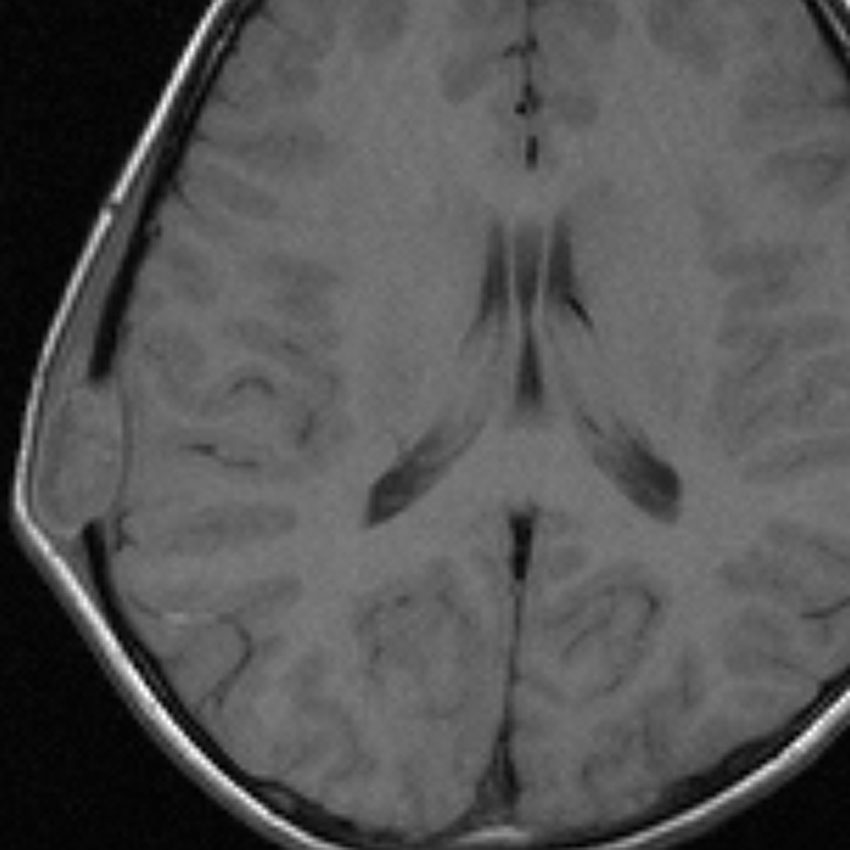

9歳の男の子です。右側頭部が腫れてきたのに気づきました。頭蓋骨のいびつな破壊像があります。

左はMRI T2強調画像です。まるで丸い腫瘍のように見えます。

下のT1強調画像では,ガドリニウム造影剤で強く増強されていて皮下に炎症性腫脹がみられ,活動期の病変であるのがわかります。

この病変は単発(孤発)病変ですが,ややいびつな形をしていて,頭皮の方に盛り上がっていますから,活動性の病変です。手術で完全摘出すると治りますから,骨欠損が広がるようなら手術したほうがいいです。理由は,手術が簡単なこと,病理診断がつくこと,これ以上の病変の広がりを抑えることです。最近は自然の骨に近いような人工骨で補填することができますが,骨形成しなくても自然修復で骨形成されます。とくに,低年齢児では骨形成をしない時もあります,頭蓋骨が自然再生するからです。